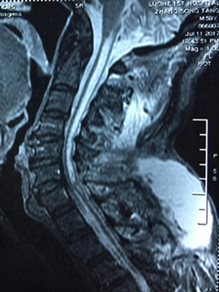

尹xx,女,35岁

患者因“突发双下肢无力3天,加重1天”入院

诊断:颈胸段椎管内髓内肿瘤

入院时患者双下肢不能行走,入院后完善相关检查,择期行手术治疗。

FullSizeRender (4)FullSizeRender (5)

术前                                   术后